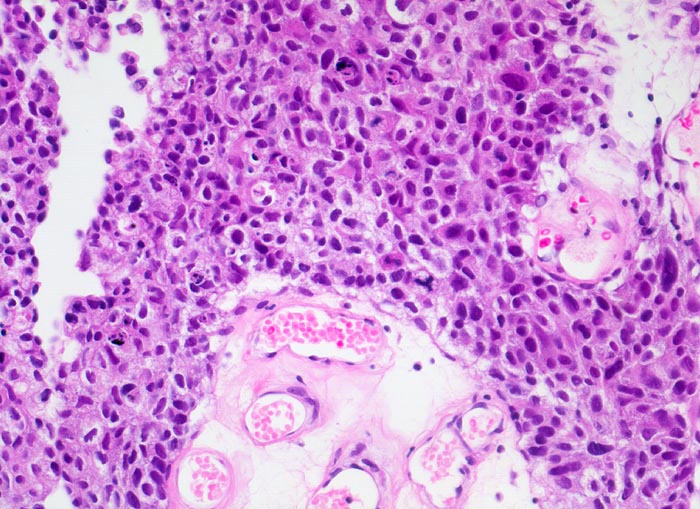

n/ Papilläres Urothelkarzinom pT1, G3

Papilläres Urothelkarzinom pT1, G3

Das Urinsediment ist wie bei den meisten papillären Tumoren zellreich. Die Atypien sind auf den ersten Blick zu sehen. Die Tumorzellen sind deutlich grösser als Basal- und Parabasalzellen. Die Kerne sind polymorph, hyperchromatisch und sehr grob strukturiert. Sie können den lavabrockenähnlichen Kernen des Plattenepithelkarzinoms gleichen. Die Kernmembran ist oft gebuchtet oder grob gebuckelt. Büschel von hochgradig atypischen zylindrischen Urothelien weisen auf die papilläre Struktur des Tumors hin. Blut und Detritus bilden den Ausstrichhintergrund.